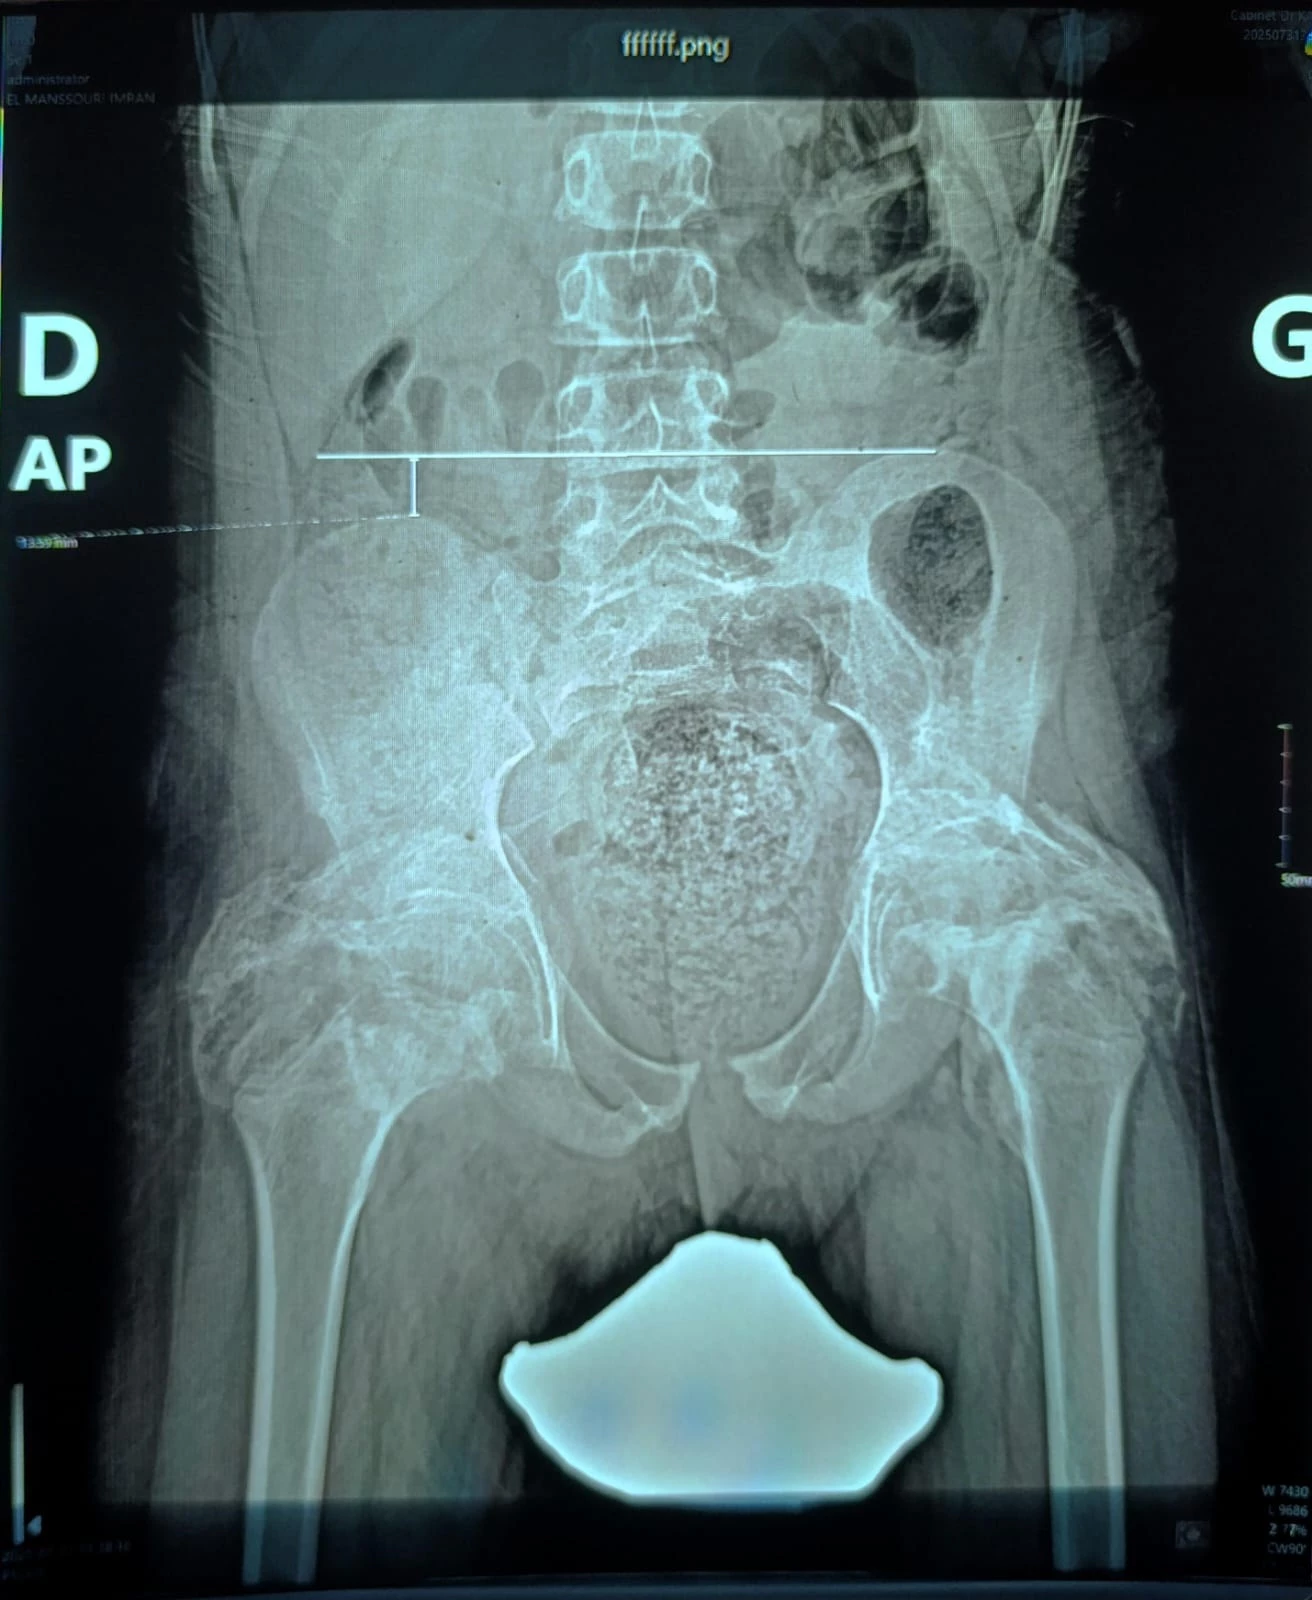

Imran es un niño que sufrió un grave accidente al derramarse agua hervida sobre su cuerpo, dejando secuelas importantes que han afectado su piel, su movilidad y su desarrollo durante su infancia. Actualmente se encuentra en tratamiento médico y podría necesitar nuevas intervenciones quirúrgicas para continuar su proceso de recuperación.

A pesar de su condición, Imran sigue siendo un niño lleno de sueños, que anhela poder vivir una infancia con la libertad de jugar y correr como otros niños de su edad. Sin embargo, el dolor físico y el impacto emocional de su situación han sido una carga muy difícil para él y su familia.

El dinero recaudado se destinará a cubrir los gastos médicos necesarios para que Imran pueda continuar su tratamiento y someterse a nuevas intervenciones quirúrgicas si son requeridas. Cada aporte ayudará a mejorar su calidad de vida y su futuro.